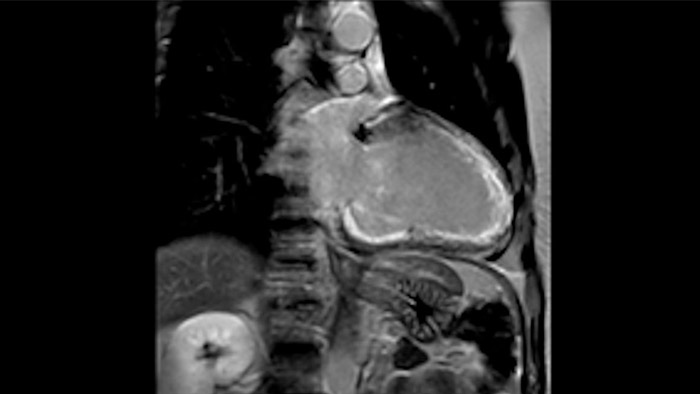

Combinando la smart-sync2 sviluppata dalla NORTHH MEDICAL (un sistema di Doppler a ultrasuoni compatibile con la MRI) con un sistema di RM Philips, abbiamo reso possibile la RM fetale cardiaca per fornire informazioni diagnostiche aggiuntive che possono aiutare nella diagnosi delle patologie cardiache congenite fetali, nel caso in cui l’ecocardiografia non sia sufficiente. Per saperne di più sullo smart-sync e scoprire cosa ne pensano i nostri clienti, clicca qui.